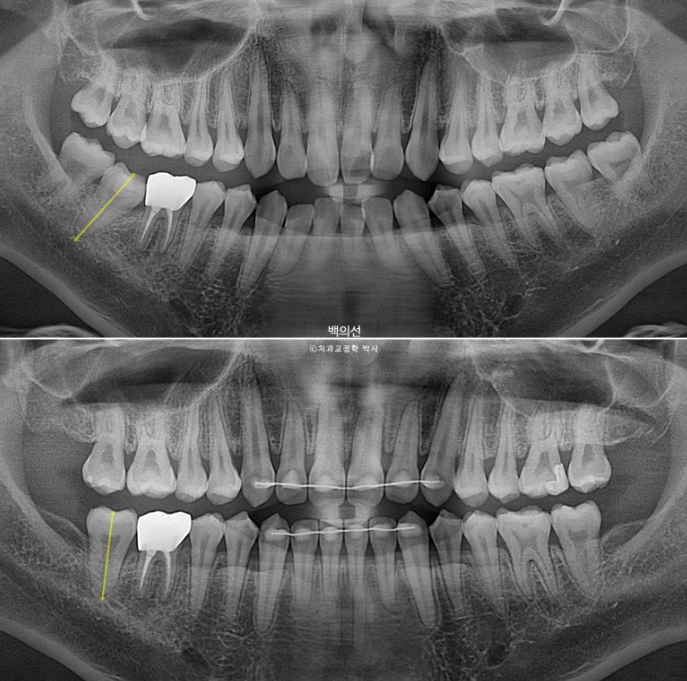

노란선이 쓰러져 있는 큰어금니죠. 사랑니를 빼고 세워야 합니다.

치근흡수는 없고 치근평행도는 좋습니다.